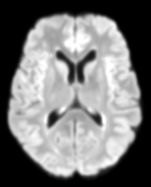

The detection of new multiple sclerosis (MS) lesions is an important marker of the evolution of the disease. The applicability of learning-based methods could automate this task efficiently. However, the lack of annotated longitudinal data with new-appearing lesions is a limiting factor for the training of robust and generalizing models. In this work, we describe a deep-learning-based pipeline addressing the challenging task of detecting and segmenting new MS lesions. First, we propose to use transfer-learning from a model trained on a segmentation task using single time-points. Therefore, we exploit knowledge from an easier task and for which more annotated datasets are available. Second, we propose a data synthesis strategy to generate realistic longitudinal time-points with new lesions using single time-point scans. In this way, we pretrain our detection model on large synthetic annotated datasets. Finally, we use a data-augmentation technique designed to simulate data diversity in MRI. By doing that, we increase the size of the available small annotated longitudinal datasets. Our ablation study showed that each contribution lead to an enhancement of the segmentation accuracy. Using the proposed pipeline, we obtained the best score for the segmentation and the detection of new MS lesions in the MSSEG2 MICCAI challenge.